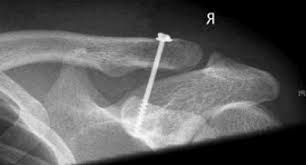

5.2.2.1. Bắt vít quạ - đòn, vòng chỉ

Kỹ thuật này là bắt vis cố định từ xương đòn xuống mỏm quạ hoặc qua nội soi buộc cố định vòng chỉ siêu bền từ xương đòn xuống mỏm quạ. Nhược điểm là cần phẫu thuật tháo vít về sau, vòng chỉ có thể cắt xương đòn và nền mỏm quạ. Phương pháp này cũng chỉ áp dụng được cho trật khớp cùng  đòn cấp tính.

Hình ảnh kết hợp xương khớp cùng đòn bằng vít quạ - đòn